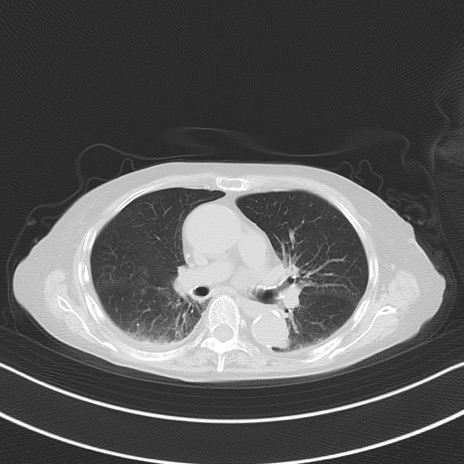

症例40(横断像)他院1日前

横断像

他院CT